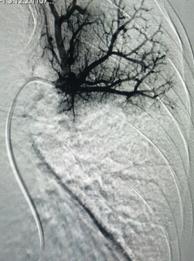

經(jīng)皮肺動(dòng)脈造影

經(jīng)綜合評(píng)估并與家屬充分溝通后,局麻下行肺動(dòng)脈造影,提示左肺動(dòng)脈主干及左肺下葉動(dòng)脈閉塞,立即予以經(jīng)皮肺動(dòng)脈栓塞導(dǎo)管介入碎栓溶栓術(shù)。在心內(nèi)科韋鋒主任、郭良玉主治醫(yī)師及成婷護(hù)師的默契配合下,爭(zhēng)分奪秒順利完成手術(shù)。術(shù)后即刻復(fù)查肺動(dòng)脈造影示左肺動(dòng)脈主干及左肺下葉動(dòng)脈恢復(fù)血流,生命體征穩(wěn)定,指脈氧恢復(fù)至100%。經(jīng)過(guò)精心治療與護(hù)理,目前患者已康復(fù)出院。